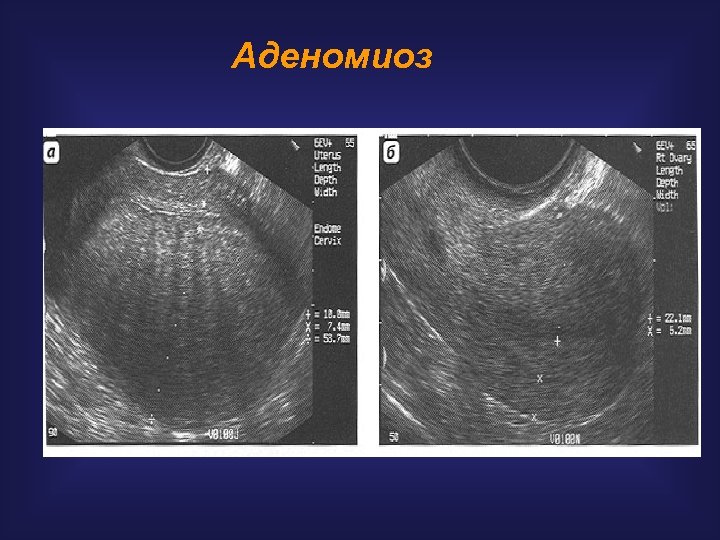

Аденомиоз